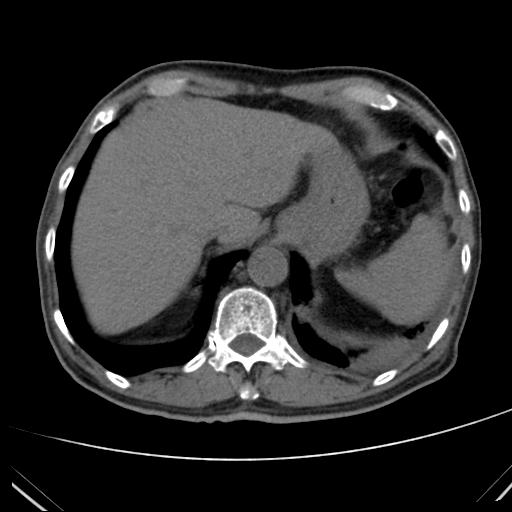

患者:男,71Y,气促10余天,PE:双肺呼吸音减弱,左肺明显,双下肺闻及少量湿性罗音。

左肺可见斑块状、斑片状索条结节状密度增高影,部分斑片影,边缘模糊,部分斑块影内见气体密度影,左下支气管狭窄。心包积液及左侧胸腔积液。考虑:左下肺阻塞性病变伴阻塞性炎症可能性大。

左肺下叶背段阻塞性病变,肿瘤可能性大,右肺小结节灶。